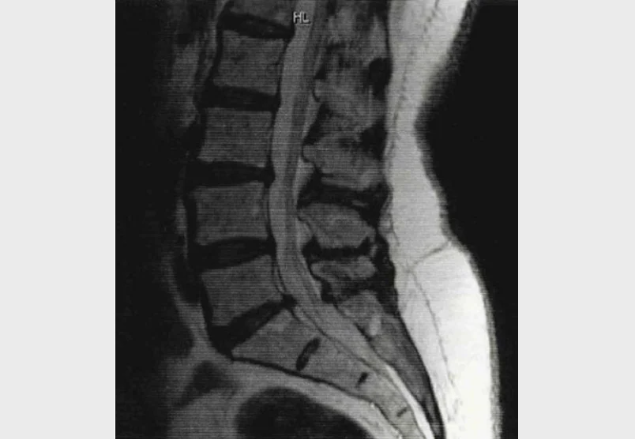

Bilateral/ unilateral leg pain or paresthesia, in the posterior aspect of the leg. Buttock pain could also indicate nerve root pain.

It is essential to rule out symptoms of cauda equina syndrome -saddle anastheisa /paraesthesia and bladder bowel disturbance (loss of control, retention, hesitancy, urgency or a sense of incomplete evacuation)

Lumbar range of movement, reflexes, dermatomes, myotomes, straight leg raise.

Important to rule out other causes of leg symptoms e.g hip joint, vascular, spinal cord compression. Objective assessment to include hip rotation, Babinski, foot and ankle pulses.